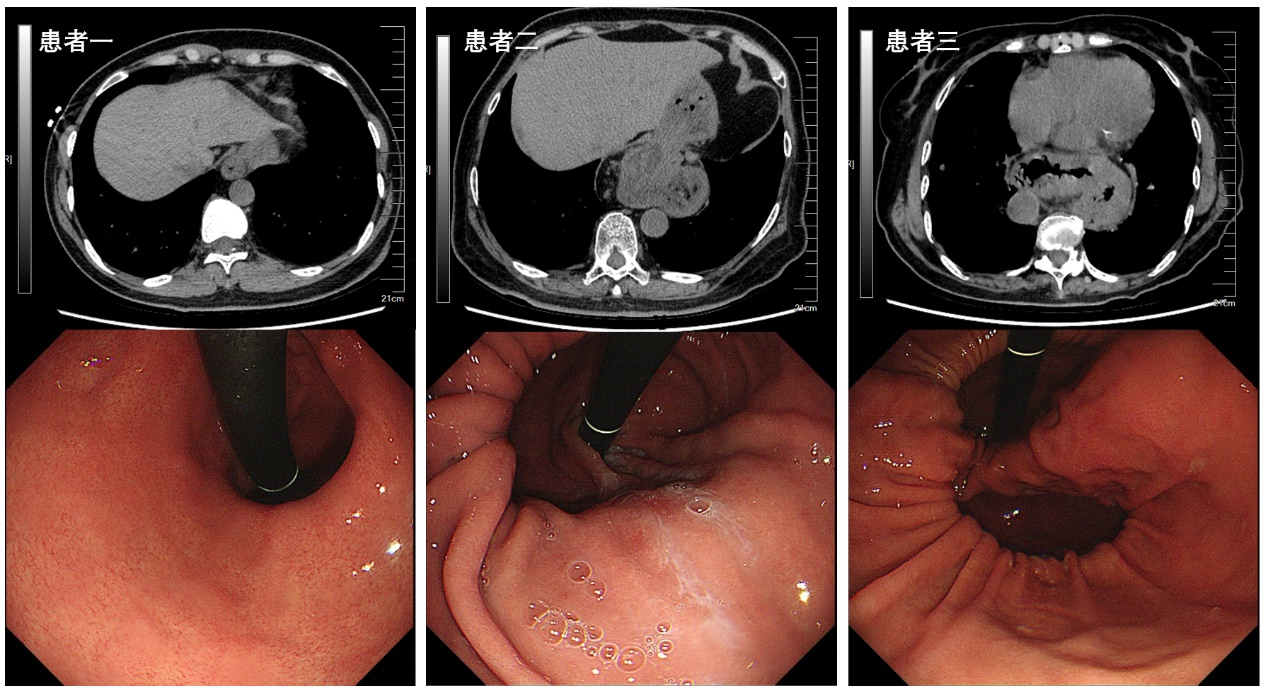

食管裂孔疝的临床诊断,通常可通过胸部 CT与胃镜检查两大核心手段明确。胸部 CT 检查可清晰显示食管裂孔增宽的形态,同时直观呈现胃、大网膜等腹腔脏器或组织疝入胸腔的范围与程度;胃镜检查时,操作者翻转镜头即可观察到贲门区域的疝囊结构,结合镜下表现即可完成明确诊断。

▲食管裂孔疝患者CT及胃镜表现

患者一:I型食管裂孔疝,主要症状为反酸、烧心;

患者二:III型食管裂孔疝,主要症状为反复便血、严重贫血;

患者三:IV型食管裂孔疝,主要症状为反复上消化道梗阻,恶心、呕吐,进食障碍。